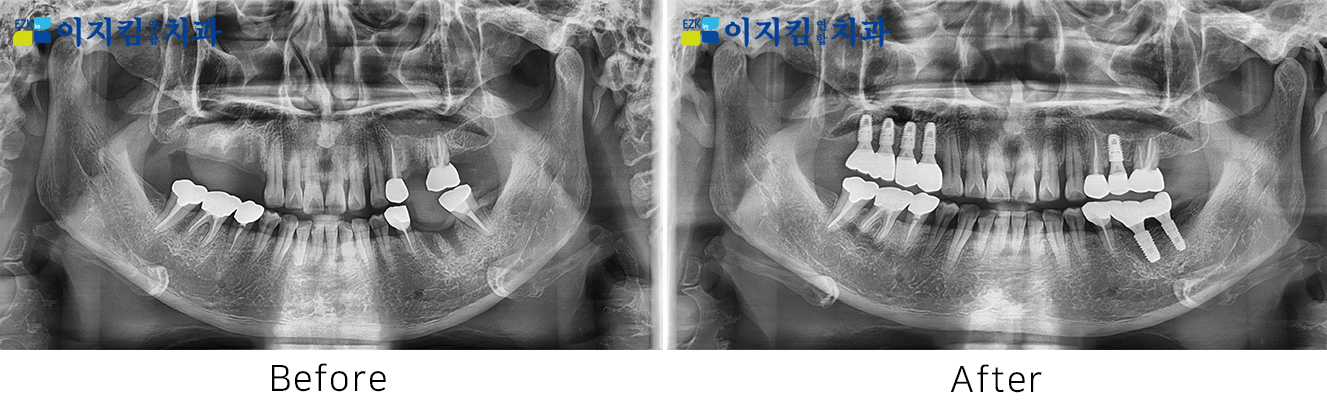

ÀÓÇöõÆ® Àü ¡¤ ÈÄ »çÁø

[

Á¶È¸¼ö : 3012

]